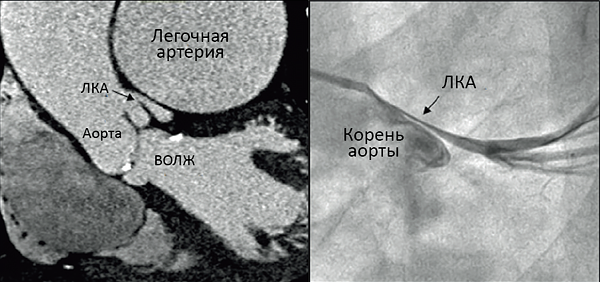

Нормальный диаметр корня аорты: медицинские нормы и отклонения